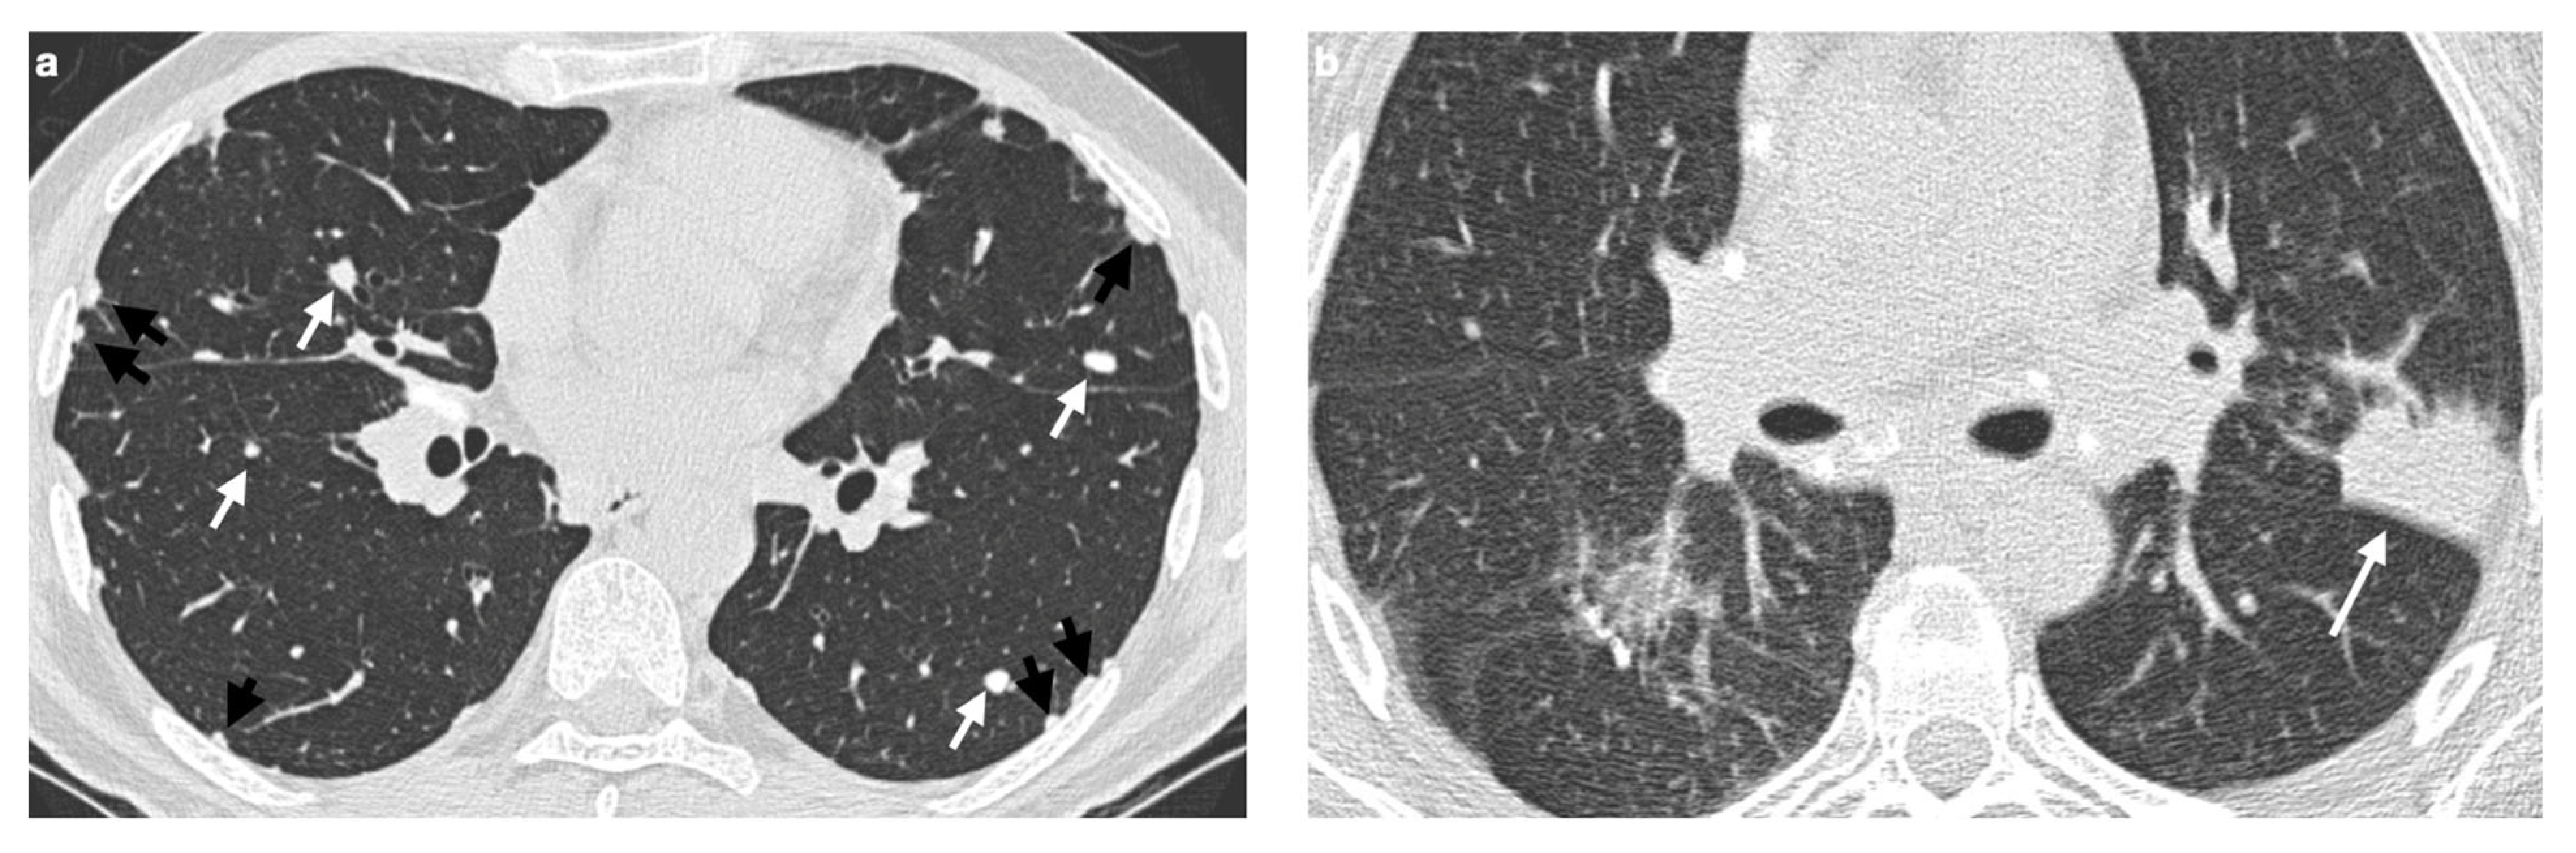

4.2. Atypical Imaging

4.2.1. Nodules and Masses

4.2.2. Patchy Parenchymal Consolidation

4.2.3. Ground-Glass Opacities

4.2.4. Miliary Opacities